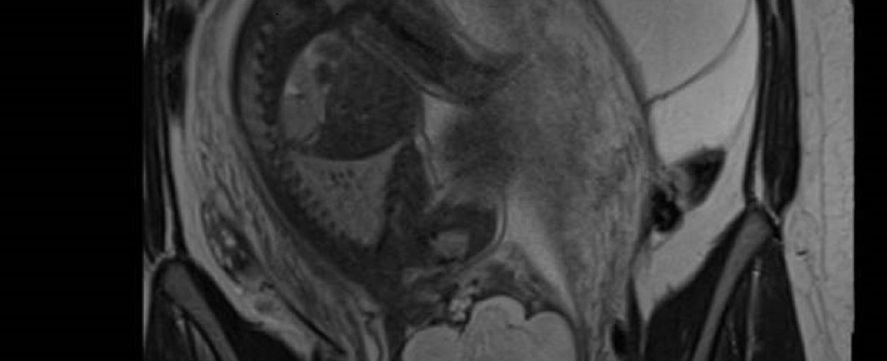

• 14h - IRM et kystes ovariens pendant la grossesse

Pre Isabelle Thomassin Naggara, Hôpital Tenon, Université Sorbonne, Paris